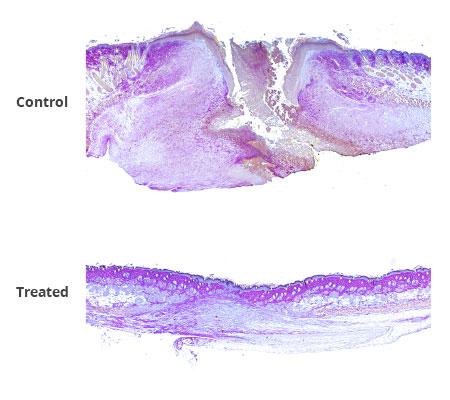

On the fourth day after mice treated for excision wounds, the open wound areas of mice in the two control groups were nearly twice as large as the wound areas in mice treated with the FL2-siRNA/PluroGel combination. Several mice treated with the combination therapy also had hair follicles present in the wound zone, while no such structures were seen in the control mice.